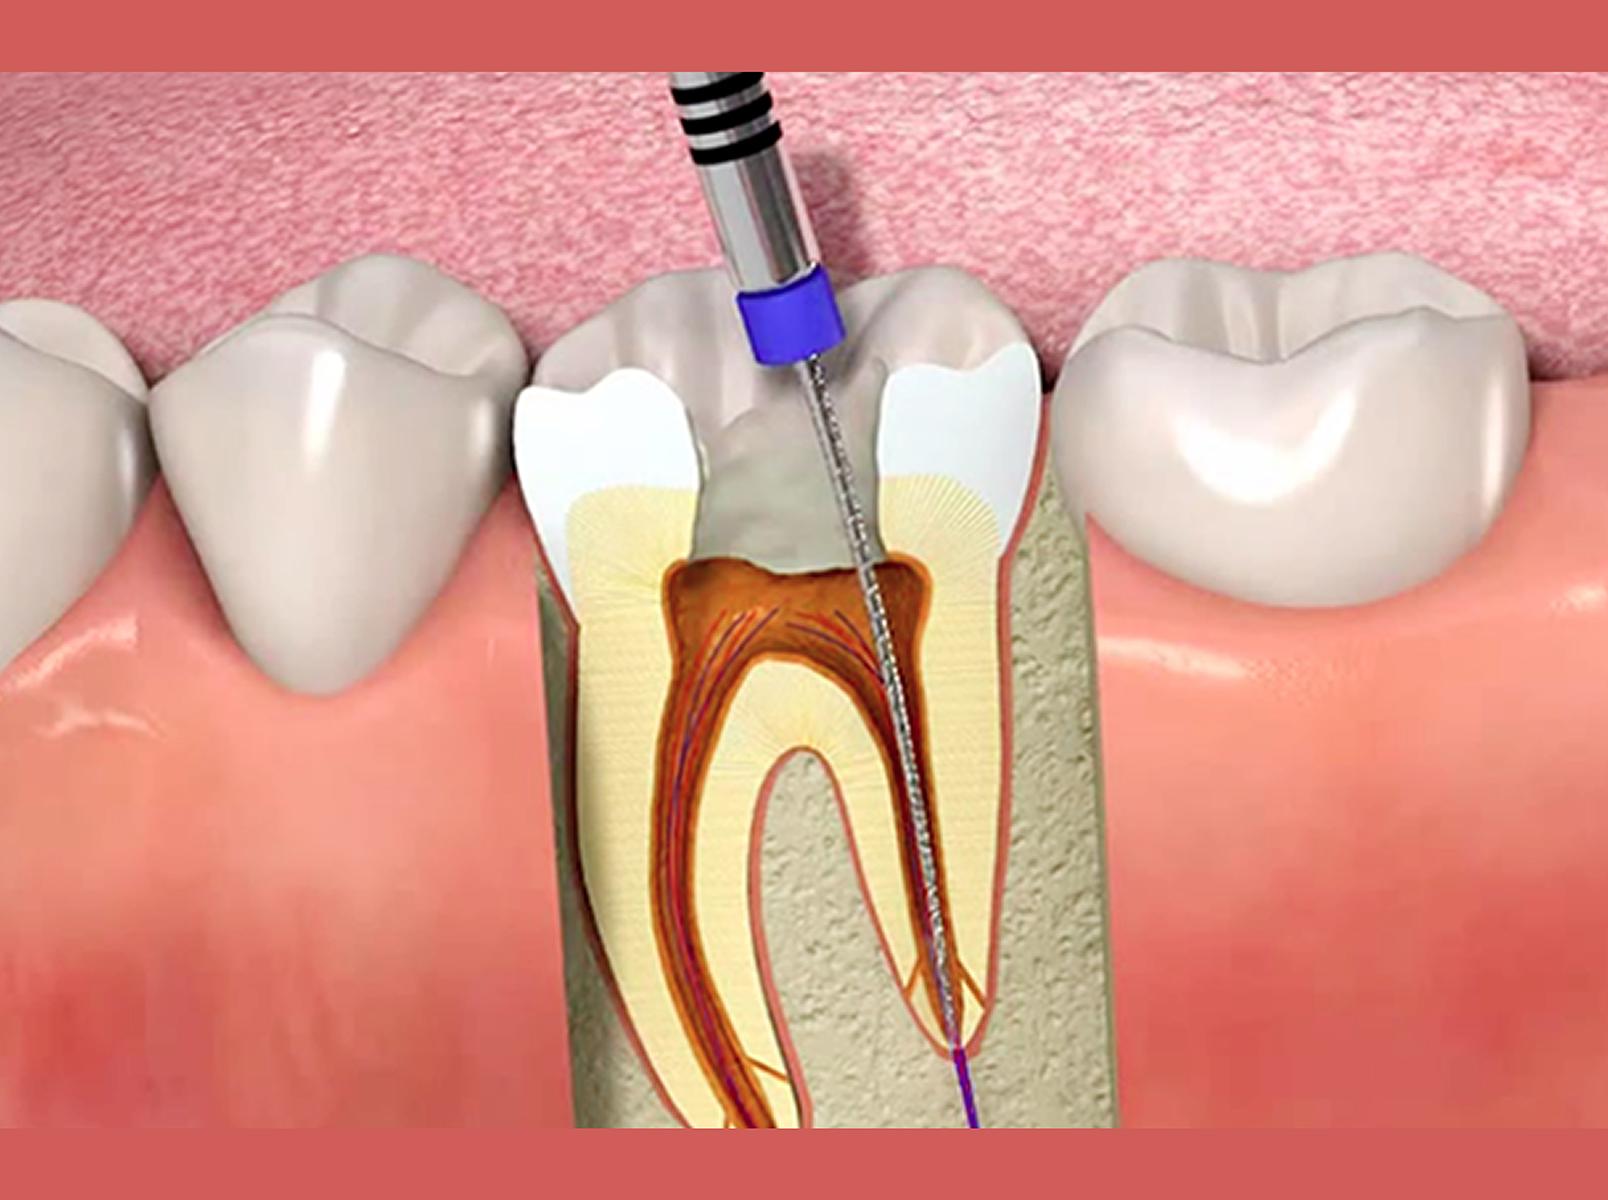

許多人得知需要進行杜牙根(根管治療)時,經常感到畏懼,然而延遲進行這項治療,或對口腔健康帶來一系列不良後果,成為潛在的威脅。儘管杜牙根治療可能讓人感到不安和焦慮,但實際上,這是一項極為安全、直接和常見的治療。

許多患者試圖推遲這項必要的治療,卻忽略了這樣做可能比治療本身更加嚴重。本文將深入探討拖延杜牙根可能帶來的後果,包括極度疼痛、牙齒損失、急性牙周膿腫、敗血症和骨質流失等。了解這些後果並提高對杜牙根治療的認識,將有助於鼓勵及時採取必要的治療,以確保口腔健康不受威脅。

答:很多人避免接受杜牙根治療的原因之一是擔心治療會很痛苦。實際上,進行杜牙根治療的感覺與填補蛀牙差異不大。儘管可能會有一些不適,但整個杜牙根治療過程中,你應該不會感到明顯的疼痛。